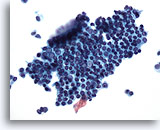

Figure 15

Peritoneal wash: Reactive mesothelial cells. 40X

Figure 15

Peritoneal wash:

Reactive mesothelial cells.

40X

This group of benign mesothelial cells also demonstrates slight overlapping. Clusters of benign mesothelial cells have a scalloped, or hobnail border, in contrast to the smooth border typically found in clusters of adenocarcinoma.